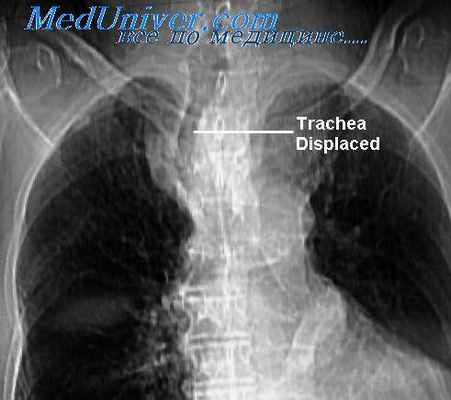

Несмотря на очень большие размеры, оно длительное время может протекать бессимптомно. Важно, что почти всегда мы можем наблюдать связь со щитовидной железой. Это образование располагается в области верхней апертуры. Может быть в переднем или заднем средостении. Как правило, оттесняет и суживает трахею, что на рентгеновских снимках создает очень характерную типичную картину.

Если вы посмотрите на обзорный снимок в прямой проекции, то сразу же будет видно, насколько изменилась конфигурация воздушного столба в трахее на уровне грудино-ключичных расчленений и выше в области верхней апертуры. Трахея оттеснена по дуге вправо и практически достигает контура средостения и несколько сужена.